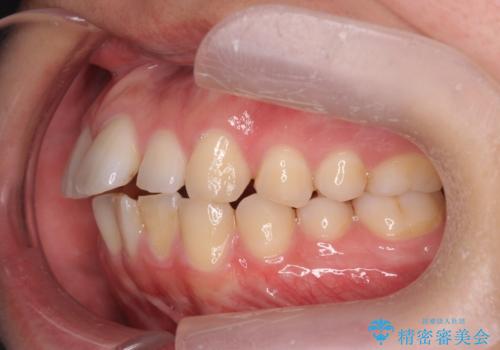

前歯が気になる。インビザラインライト

- 前歯が気になるとの事で来院。

矯正を希望されたが費用と時間を抑えたいとの事でインビザラインライトで矯正を行いました。(奥歯の位置関係はほぼ変えない)

前歯が綺麗に並び大変満足して頂けました。